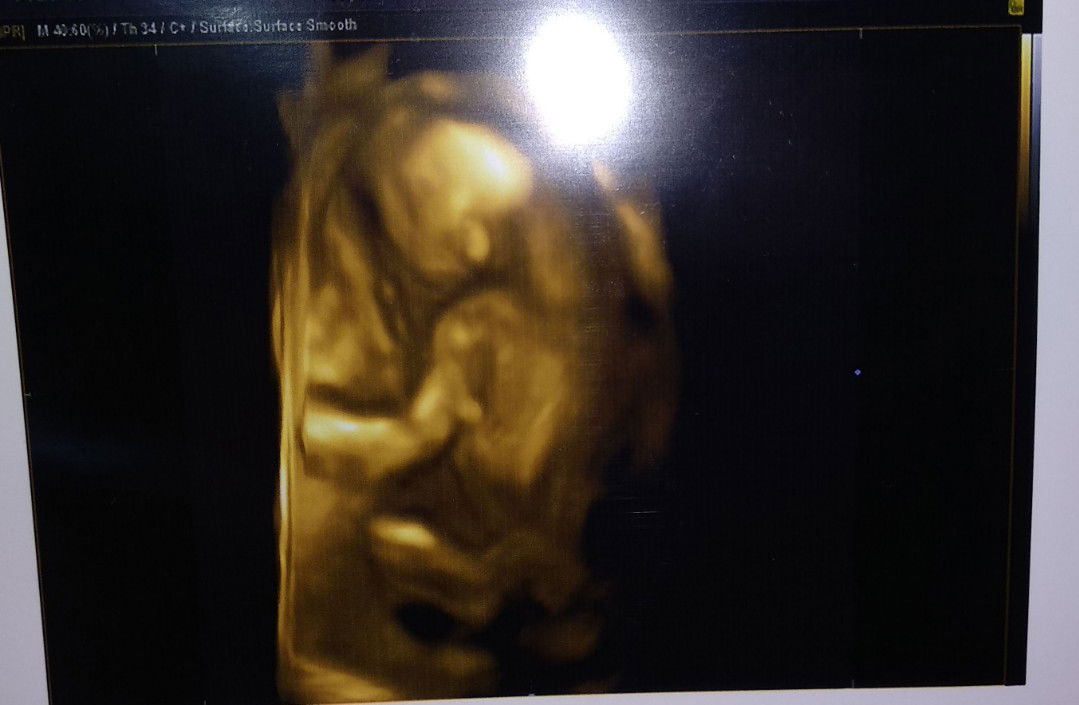

usg

Alhamdulillah, kemarin usg 4d dikehamilan 19w karena khawatir jaga-jaga ada kondisi dede diperut yang saya ga ketaui karena sebelumnya ke puskesmas dibilang ga kedengeran djj si dede.Masya Allah seseneng itu liat didalam, kata dokter Alhamdulillah sehat semua cuma sayang dia munggungin, digoyang²in perut saya pun dia ga mau pindah dari posisi tengkurap.Dan sekarang si Dede udah mulai kerasa kalau gerak, padahal sebelumnya ga pernah kerasa ??? Semoga calon dede bayi kita sehat² semua ya bun.aamiin allahumma aamiin